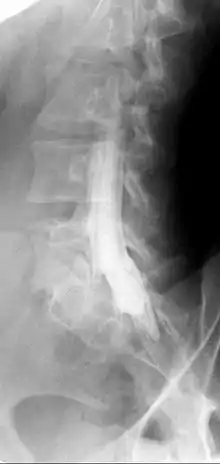

تصوير النخاع: هو نوع من الفحص الشعاعي الذي يستخدم مادة ملونة اليود للكشف عن أمراض الحبل الشوكي بما في ذلك تشخيص موقع إصابة الحبل الشوكي، والأورام.[1][2][3]

تصوير النخاع يستخدم في تشخيص عن العيوب التي تصيب الحبل الشوكي والقناة الشوكية والجذور العصبية الشوكية والأوعية الدموية التي تزود النخاع الشوكي وتضيق القناة الشوكية والأورام وغيرها.

التصوير بالرنين المغناطيسي (MRI) غالبًا ما يكون أول فحص تصوير يتم فحص لتشخيص الحبل الشوكي وجذور الأعصاب. ومع ذلك، في بعض الأحيان، يكون المريض لديه جهاز طبي مثل جهاز تنظيم ضربات القلب، قد يمنعه من هذا فحص التصوير بالرنين المغناطيسي. في مثل هذه الحالات، يتم فحص تصوير النخاع عن طريق الأشعة المقطعية بدلاً من التصوير بالرنين المغناطيسي لتشخيص الفقرات العنقية أو الفقرات الصدرية أو الفقرات القطنية أو تضيق العمود الفقري بشكل أفضل. وكما موضح في شكل صورة (2).